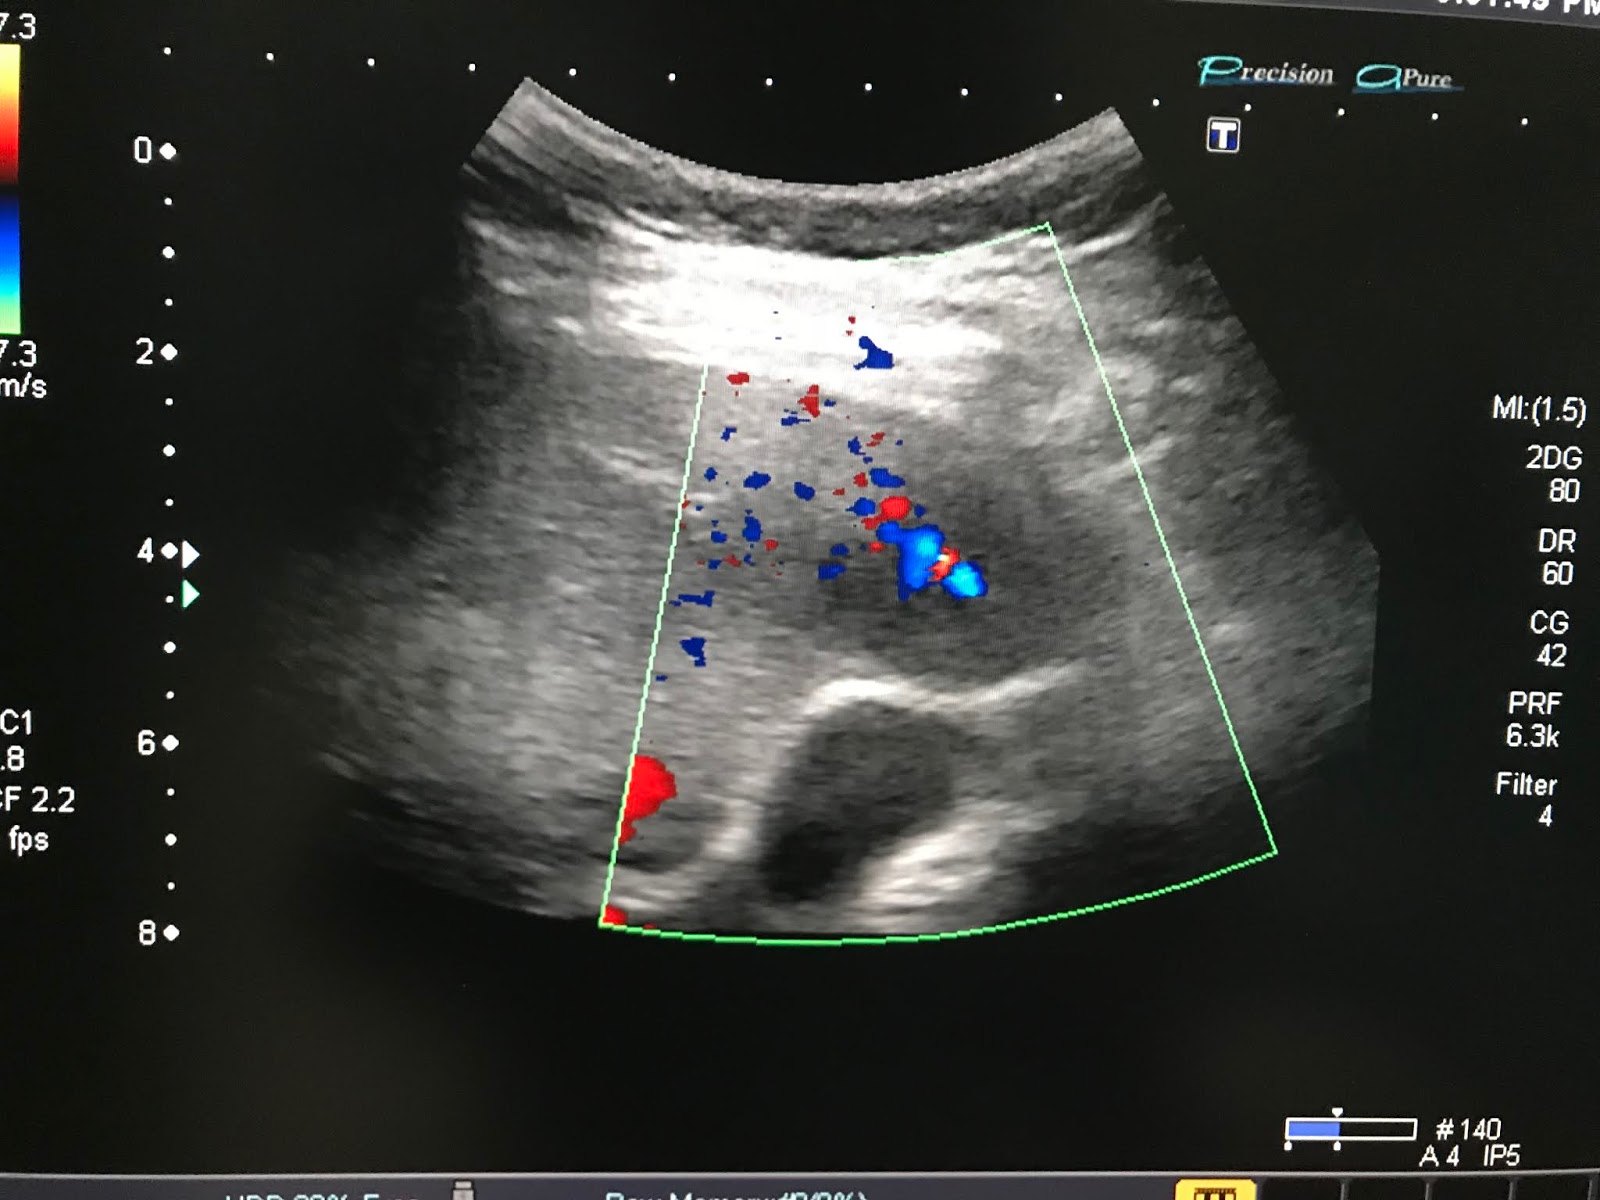

VIETNAMESE MEDIC ULTRASOUND CASE 673 RENAL INFARCTION, Dr PHAN THANH Medic Medical Diagnostic Center Vietnam Phạm vi được công nhận. Công ty tnhh y tế hoà hảo. công ty tnhh lab group international việt nam. medic lab (medic medical center) cơ quan chủ quản: Vilas med 041 hiệu lực công nhận/ period of accreditation: dịch vụ khám bệnh và kỹ thuật chẩn đoán. Hãy tải app “”medic hòa hảo”” đăng ký sử. Medic Medical Diagnostic Center Vietnam.

From www.ultrasoundmedicvn.com